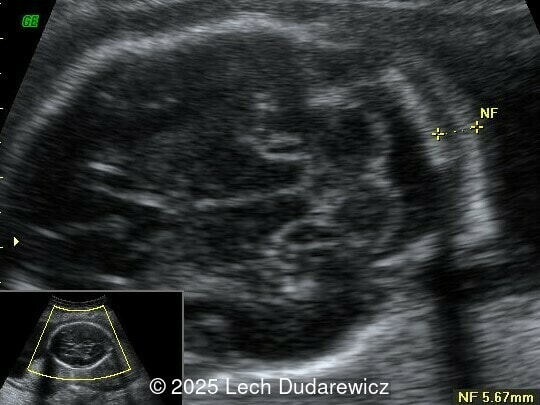

Image 2

Structural anomalies were observed in multiple organ systems. The fetal skeleton showed hypoplastic iliac bones, rib deformities, hypoplastic scapulae, and excessive cervical spine lordosis. The fetal hands exhibited abnormal alignment of the fingers with restricted movement, and both feet were clubbed. Subcutaneous edema was noted over the forehead and occiput with a small cystic hygroma, along with increased nuchal fold thickness at 5.6mm, indicative of soft tissue edema.  Additional abnormalities included mild pyelectasis. The fetal stomach appeared nearly empty, likely reflecting impaired swallowing or associated anomalies. Polyhydramnios was also noted. External male genitalia appeared normal. Cardiac evaluation revealed multiple echogenic foci within the left ventricle and an atrioventricular septal defect. While the heart's overall structure and function were otherwise normal, these findings added to the overall suspicion of a syndromic condition.

Other findings on prenatal ultrasound include soft tissue edema, facial anomalies, cardiac defects, and renal abnormalities. Soft tissue findings, including increased nuchal fold thickness and generalized subcutaneous edema, are common in campomelic dysplasia. Macroglossia and facial dysmorphisms, such as a flat nasal bridge or hypertelorism, may be observed but can be subtle on prenatal imaging. Polyhydramnios, frequently noted in affected pregnancies, may result from impaired fetal swallowing due to craniofacial or neurologic abnormalities. Cardiac anomalies, while not pathognomonic, include ventricular septal defects and echogenic intracardiac foci. Renal abnormalities, such as pyelectasis or enlarged kidneys, may also be present. These findings, although non-specific, contribute to the syndromic picture of campomelic dysplasia.